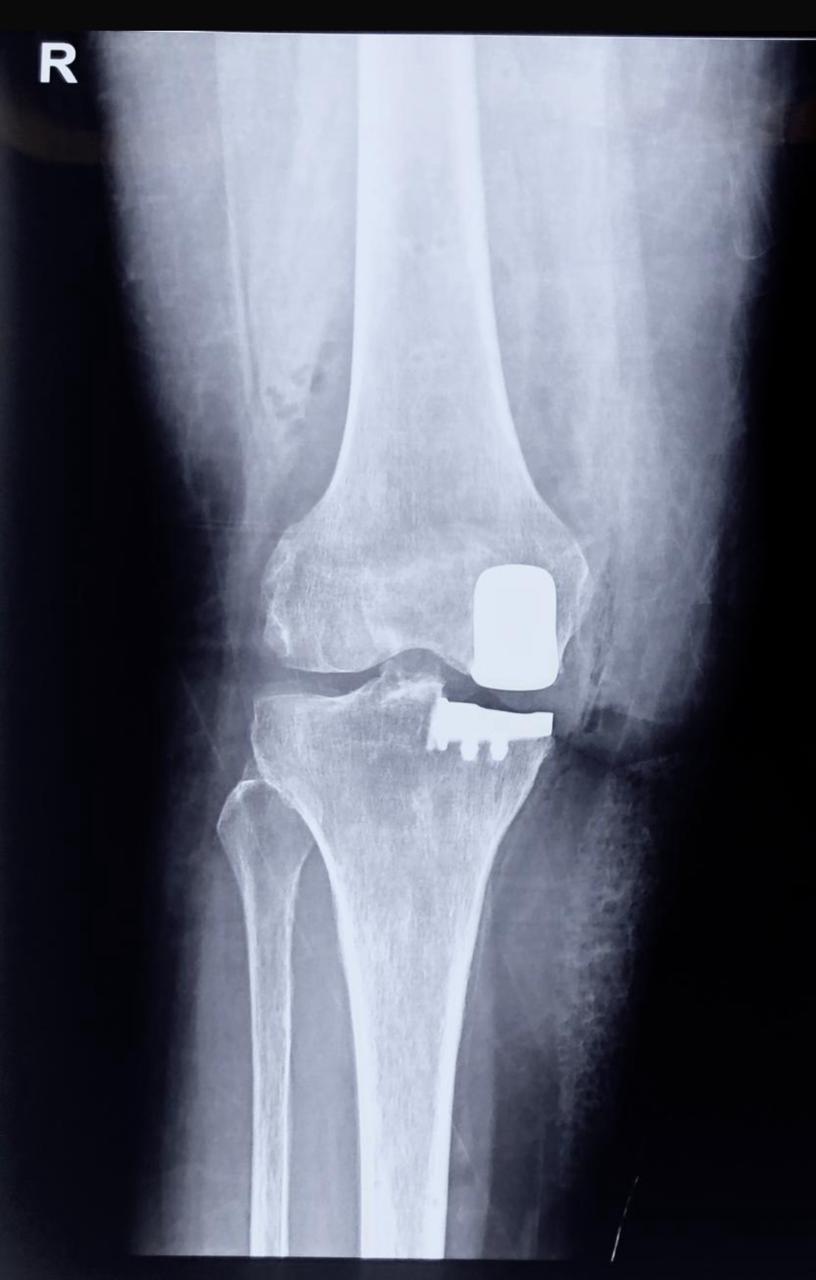

In a normal knee, the bone ends do not touch each other because they are covered by a thin cushion called cartilage, which appears as a space between the bones on X-rays. Arthritis is the wear-and-tear of the cartilage in one part of the knee (called a ‘compartment’), while the other two compartments remain healthy.

In Unicompartmental Knee Resurfacing (or partial knee replacement), only the worn cartilage in one compartment is resurfaced with metal and polyethylene, while preserving the rest of the normal knee. By resurfacing only one compartment at the right time, the normal knee joint is preserved, and a total knee replacement can be avoided or delayed for over 15 years.